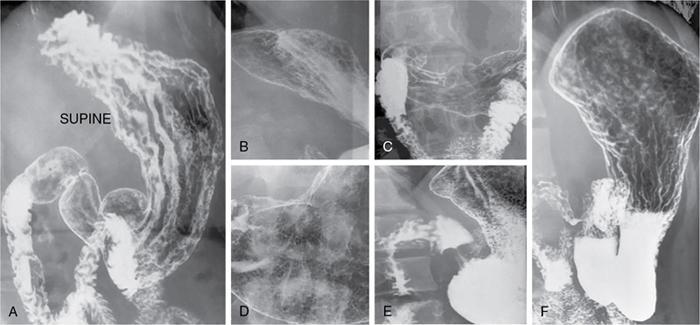

Swarup Nellore, Soumil Vyas, Ujwal Bhure, Ankit Jain, Richa Kothari, Daksh Mehta, Divya Kantesaria, Disha Lokhandwala, Karthik Ganesan The stomach is the most dilated portion of the gastrointestinal tract positioned between the oesophagus and the small intestine occupying the epigastrium, left hypochondrium and umbilical regions of the abdomen performing a multitude of functions including storage and mixing of food and controlling the passage of food into the intestine. Anatomically, the stomach is divided into the following parts (Fig. 8.2.1): the gastric cardia is the portion immediately adjoining the oesophageal opening into the stomach. The fundus is the dome-shaped part above the horizontal plane of the cardiac orifice which undergoes receptive relaxation and is the site of the autonomic pacemaker. The body is the largest part of the stomach extending from the cardiac orifice to the level of incisura angularis (notch like bend in the mid lesser curvature) containing majority of parietal cells (which secrete hydrochloric acid), chief cells (pepsinogen) and enterochromaffin-like cells (ECL). The pylorus is the tubular distal portion of the stomach which is further divided into the gastric antrum and pyloric canal. The pyloric antrum containing G-cells producing gastrin extends from the incisura angularis up to the pyloric sphincter which is an anatomical sphincter formed by concentric thickening of the circular muscle coat and encircles the narrow-slit like pyloric canal. The left dome of diaphragm and oesophagus lie superior to the stomach while the greater omentum and pancreas lie inferiorly. Spleen and liver lie on either side laterally while the transverse mesocolon is located inferolaterally. Diaphragm, greater omentum, left lobe of liver and anterior abdominal wall are anteriorly related to the stomach and contents of lesser sac including pancreas, spleen, splenic artery, transverse mesocolon, left kidney and adrenal gland lie posteriorly. The stomach is embryologically derived from the primitive foregut and is suspended anteriorly by the ventral mesogastrium and posteriorly by the dorsal mesogastrium. During development as the stomach rotates, the peritoneum grows and condenses to form perigastric ligaments, which contain blood vessels, lymphatics, lymph nodes, nerves and fat. The liver forms in the ventral mesogastrium, which develops into the falciform ligament, gastrohepatic ligament (GHL) and hepatoduodenal ligament (HDL). The spleen and pancreas form within the dorsal mesogastrium, which fuses with the posterior abdominal wall to form the gastrocolic ligament (GCL), gastrosplenic ligament (GSL) and splenorenal ligament (SRL). The perigastric ligaments are identified anatomically by the vessels contained in them (Fig. 8.2.2). The gastric cardia and lesser curvature of the stomach are attached to the inferior surface of liver by the lesser omentum by the gastrohepatic ligament respectively which contains the left and right gastric vessels. The inferior free edge of the gastrohepatic ligament extends inferiorly as the hepatoduodenal ligament between the porta hepatis and proximal duodenum gastrophrenic ligament extends between the stomach and the left hemidiaphragm. The gastrocolic ligament identified by the left and right gastroepiploic vessels, connects the greater curvature of the stomach to the anterior surface of the transverse colon. This ligament extends inferiorly as the greater omentum which is a double-layered peritoneum forming a drape anterior to the bowel loops. The gastrosplenic/lienogastric ligament bridges the posterolateral wall of the fundus and greater curvature along the proximal body of the stomach to the splenic hilum and contains the short gastric vessels. The gastrosplenic ligament is contiguous with the lienorenal ligament and both these structures constitute the lateral boundary of the lesser sac. Macroscopically the stomach shows a thick vascular mucosal lining in the form of longitudinal folds called gastric rugae. Microscopic layers of the stomach include mucosa, submucosa, muscularis externa and serosa. The mucosa includes surface mucus cells with simple columnar epithelium, gastric pits, gastric glands, lamina propria and muscularis mucosa. Submucosa includes connective tissue with submucosal Meissner’s plexus. Muscularis externa comprises three smooth muscle layers (longitudinal, circular and oblique) and Auerbach myenteric plexus. The outermost layer called serosa consists of loose connective tissue and visceral peritoneal lining. The arterial supply of stomach is constituted by the branches of celiac artery predominantly in the form of two anastomotic arcades along the lesser and greater curvature. Left gastric artery, a direct branch of the celiac trunk supplies the upper part of the lesser curvature while the lower part is supplied by the right gastric branch of the common hepatic artery arising at the upper border of pylorus. The left gastroepiploic artery, a branch of splenic artery, supplies the upper part of greater curvature and the inferior portion is supplied by the right gastroepiploic artery which is a branch of the gastroduodenal artery. The fundus additionally receives few small short gastric branches from the splenic artery. The veins follow the arteries in their nomenclature. Left and right gastric vein show direct drainage into the portal vein. The splenic vein derives flow from the short gastric and left gastroepiploic vein whereas the right gastroepiploic vein drains into the superior mesenteric vein. Pylorus can be surgically delineated by the prepyloric vein of Mayo lying on its anterior surface. Intrinsic nerve supply consists of the myenteric plexus of Auerbach and submucosal plexus of Meissner. Extrinsic nerve supply consists of sympathetic and parasympathetic components. Sympathetic nerve supply arises from T5 to T9 spinal cord segments supplying the celiac plexus via the greater splanchnic nerve. The plexuses then travel along the respective branches of celiac artery supplying the stomach. Parasympathetic nerve supply is derived from oesophageal plexus of vagus dividing into two vagal trunks. Right (posterior) vagus gives off the posterior gastric branch also called the criminal nerve of Grassi supplying the cardia and fundus of stomach. Right vagus then gives off a celiac branch and continues along lesser curvature of stomach as the posterior gastric nerve of Latarjet supplying the antrum, body and pylorus. Left (anterior) vagus gives off a hepatic branch then continues along the lesser curvature as the anterior nerve of Latarjet supplying the antrum, body and pylorus. Crow’s feet innervation to antropyloric area are important surgical landmarks preserved during highly selective vagotomy receiving branches from both major nerve trunks (anterior and posterior) at the incisura angularis. Anatomical lymphatic drainage is divided into three areas. Area I is the superior two-thirds of stomach draining via the nodes along left and right gastric vessels into the aortic nodes. Area II includes the right two-thirds of the inferior one-third which drains through the nodes along right gastroepiploic vessels via the subpyloric nodes into aortic nodes. Area III includes left one-third of greater curvature draining via short gastric and splenic nodes into suprapancreatic nodes and ultimately into aortic nodes. Gastric lymph node stations are divided into 4 levels with 16 lymph node stations: Paraesophageal nodes below the diaphragmatic hiatus (17) and above the diaphragmatic hiatus (18) are also included. The stomach first appears as a fusiform dilatation in the distal endodermal foregut in the 4th week of embryonic life. The dorsal and ventral mesogastrium suspend the developing stomach to the respective abdominal walls. Preferential growth along the dorsal border of the developing stomach leads to the formation of a convex dorsal border (greater curvature) and a concave ventral border (lesser curvature). The stomach subsequently undergoes a sequence of rotations. The first (90 degrees) clockwise rotation occurs around the longitudinal axis which brings the lesser curvature to the right and greater to the left. This rotation also brings the dorsal mesogastrium towards the left and ventral to the right creating a space behind the stomach called as the lesser sac or omental bursa. The second clockwise rotation occurs around the anteroposterior axis, with the caudal or pyloric part moving upwards and to the right while the cephalic or cardiac portion moves towards the left and slightly downward causing the stomach to assume its final anatomic position. This rotation causes the dorsal mesogastrium to bulge downwards and grow further to eventually become a double-layer apron called the greater omentum. The developing liver divides the ventral mesogastrium into the falciform ligament extending from the ventral abdominal wall to the liver with its lower free edge forming the ligamentum teres, the visceral peritoneum surrounding the liver and the lesser omentum with its two parts – the hepatogastric ligament and hepatoduodenal ligament. The dorsal mesogastrium gives rise to the redundant greater omentum, gastrocolic ligament, gastrosplenic ligament and lienorenal ligament. These perigastric ligaments help us in deciphering patterns of the spread of gastric malignancies and in taking decisions regarding their management and prognostication. These will be further explained in detail under the section of gastric malignancies. An abdominal radiograph is often the initial imaging test for evaluation of acute abdominal pain. The gastric bubble is seen below the left hemidiaphragm in situs solitus. Presence of gastric outlet obstruction may show a distended stomach with gasless small bowel. Hollow visceral perforation is diagnosed by free air seen under domes of diaphragm. Also, the presence and position of various tubes like the nasogastric tube can be confirmed using a radiograph. A fluoroscopic upper gastrointestinal (GI) examination is the radiological study of oesophagus, gastro-oesophageal junction, stomach, duodenum up to duodenojejunal junction by oral administration of contrast. Barium sulphate is a good contrast medium for GI studies as it is radio-opaque, non-absorbable, inert to tissues and can be used for double-contrast studies. Patient should be nil by mouth at least 4 hours prior to the examination. In a single contrast examination, the emphasis is on mucosal relief, luminal distention with contrast material and compression. In the erect position, a small amount of contrast is given to swallow while the oesophagus is visualized under fluoroscopy. The table is then made horizontal and the patient is rotated in a clockwise manner as seen from the foot end of the patient, thus ensuring good coating of the stomach mucosa. Mucosal relief images are then obtained in supine and prone positions to demonstrate the mucosal fold pattern and possible filling defects. After giving some more contrast, the patient is turned oblique with the right side dependent and spot images of the duodenal cap and C loop are taken both in distended and empty states. The patient is again positioned erect and more images of duodenal cap and loop are taken. Further contrast is given to optimally distend the lumen and assess for possible contour abnormalities, wall rigidity and strictures. Compression techniques help assess for filling defects and lesions, in the compressible areas of the stomach. Images are taken in multiple positions – supine, prone, right anterior oblique, right lateral, left posterior oblique in recumbent and right anterior oblique in erect position. Gastric peristalsis and emptying can be observed at fluoroscopy. Advantages of the single contrast technique are that it can be performed quickly, well-tolerated and requires less patient cooperation as compared to double-contrast studies. It can even be performed in physically debilitated patients. Barium is contraindicated in suspected cases of perforation, aspiration, fistula or recent GI biopsy. Single contrast examination can be performed using water-soluble iodinated contrast media in these cases and immediate postoperative patients. Earlier, ionic contrast like Gastrograffin was used. However, due to its high osmolarity, nowadays, non-ionic contrast is preferred as it causes less electrolyte imbalance due to its low osmolarity. Also, it delineates the GI tract very well due to less dilution. Double-contrast studies provide better evaluation of the mucosa than do single-contrast studies. Here, the emphasis is on coating the mucosa with barium and distending the lumen with gas. A well-performed double-contrast study is biphasic and also incorporates some single-contrast techniques. The initial part of the examination is the same as a single contrast examination to obtain the mucosal relief images. Then, gas-forming powder that produces carbon dioxide within the stomach lumen is given with more barium. With the double-contrast technique, the mucosa is coated with a high-density barium suspension and the lumen distended with gas. The patient is rotated in a clockwise manner as seen from the foot end of the patient, thus ensuring good coating of the stomach mucosa. Spot images of the distended stomach are taken followed by the duodenal cap and loop in oblique right-side dependent position. Patient is brought back to erect position erect and more images of stomach, duodenal cap and loop are taken. Further contrast is given to distend the lumen. Residual fluid or food debris in the stomach impairs stomach coating, and lack of adequate coating may preclude visualization of lesions. In addition, optimal gaseous distention is important as underdistention will cause a false appearance of abnormally thickened, and overdistention can obliterate abnormal folds. With normal gastric anatomy, the gastric fundus is best visualized in the upright left-posterior-oblique position, the body in the supine anteroposterior position and the antral-pyloric region in the supine left-posterior-oblique position. The normal gastric mucosal surface should be smooth on double-contrast studies. Areae gastricae appear as reticular networks of polygonal tufts which, owing to the presence of barium in the narrow intervening grooves, are coated with white lines. These are seen most often in the antrum or body of the stomach but can also be seen in the fundus. Areae gastricae are identified on double-contrast studies in 70% of patients and are seen more often in elderly patients. Polygonal tufts should normally range in size from 2 to 3 mm in the antrum and 3 to 5 mm in the body and fundus. Normal gastric folds are more prominent in the proximal to mid stomach and more undulating along the greater curvature as compared with the lesser curvature. Antral folds should be typically effaced with the double-contrast technique. Gastric cardia is characterized by three or four stellate folds radiating from a central point at the gastro-oesophageal junction; this is known as the cardiac rosette and is best visualized in the supine right-lateral position. Ultrasonography (USG) is the modality of choice to visualize hypertrophic pyloric stenosis in infants. Although USG does not play much of a role in adults for imaging of stomach due to reflection of sound waves by air, luminal distension with water may enable to identify mucosal – submucosal pathologies and to assess perigastric relationships in pathologies. CT can not only evaluate the location and anatomy of the stomach, but also provide additional information about the relationship of the stomach to surrounding structures. An optimal CT examination of the stomach includes good stomach distension with a well-visualized wall. Gastric distention can be achieved by the oral administration of negative or positive luminal contrast. Positive contrast agents include a 1%–2% barium suspension or a 2%–3% solution of a water-soluble iodinated contrast agent. Water-soluble agents should be used in cases of suspected perforation. Positive agents provide a bright lumen with better identification of luminal encroachment or diverticula but may limit detailed evaluation of gastric wall enhancement. Positive contrast also may not mix well with gastric contents, producing a pseudotumor appearance. On the other hand, neutral or negative contrasts agents, usually water, produce a low attenuation lumen which allows for more detailed evaluation of the gastric wall and its enhancement pattern following intravenous contrast and is preferred for three-dimensional imaging. Multidetector CT with thin collimation allows for postprocessing in any orthogonal plane. The CT data of the stomach can be manipulated to simulate endoscopic images (virtual gastroscopy). This display technique accentuates the stomach wall and folds. Prior to evaluating the stomach with CT, oral contrast is administered at repeated intervals as well as immediately prior to scanning. Multiphasic scanning after intravenous contrast may be employed at 25–35 seconds (late arterial), 55–75 seconds (venous phase) after contrast injection. Normally, the gastric wall may enhance to approximately 120 Hounsfield Units after intravenous contrast administration. The mucosa may enhance more than the relatively lower-attenuation muscularis propria. Abnormal enhancement of the wall can highlight pathologic processes. The CT appearance of the stomach also depends upon the degree of distention. When well distended, the body and fundus is less than 5 mm thick, though the normal antrum may appear slightly thicker. The presence and pattern of wall enhancement, degree and location of wall thickening, and length of an involved segment may be assessed. Comprehensive MRI examination of the stomach and duodenum by the combined use of T2-weighted single-shot and T1-weighted gradient echo (GRE) – with and without fat suppression, and gadolinium-enhanced 3D GRE helps to detect the spectrum of gastric diseases on MRI. These sequences minimize artefacts from bowel peristalsis, increase the sensitivity of detection of peritoneal and serosal disease by suppressing the high signal of intra-abdominal fat, widen the dynamic range of abdominal tissue signal intensities and distinguish between intraluminal bowel contents and bowel wall. The gastric rugae are well seen on T2-weighted single-shot spin-echo images and their enhancement appears as bands of enhancing tissue arranged perpendicular to the external contour of the gastric wall. The normal gastric wall enhances more intensely than other segments of bowel on immediate postgadolinium SGE images. Water is frequently used as an oral contrast agent when imaging the upper GI segment-stomach and duodenum. Noninvasive dynamic study for assessment of gastric motor function and wall motility can also be done using MRI for diagnosis of gastroparesis. Gastric emptying scintigraphy (GES) is a well-established radionuclide procedure to evaluate patients with suspected gastric motility disorder, more so for non-invasive assessment of gastroparesis in patients with symptoms of postprandial fullness, nausea, vomiting, abdominal pain, bloating, early satiety, loss of appetite, as well as weight loss. Gastroparesis, commonly seen in diabetics, is a condition that affects the normal spontaneous movement of the gastric muscles, leading to impairment of gastric motility, because of which the stomach cannot empty itself of food in a normal fashion and time. GES can also provide useful information with regards to assessment of impaired gastric motility in patients with GERD (gastro-oesophageal reflux disease) unresponsive to routine therapy, diabetics with poor glycemic control, and also in patients with colonic inertia who are being considered for colectomy (since benefits of colectomy are mitigated in patients with concurrent impaired gastric emptying). On the other hand, GES is also useful for assessment of rapid gastric emptying (GE), which is a major factor in dumping syndrome, often seen post peptic ulcer surgery, with or without vagotomy. The solid or liquid component of a meal is radiolabelled with a radiopharmaceutical, which is consumed by the patient and subsequently measured gastric radioactive counts by scintigraphy correlate with the volume of the meal remaining in the stomach. Solid-phase GES is used for the evaluation of gastric motility disorder/gastroparesis. Liquid-phase gastric emptying is generally not clinically useful since it is often in the normal range in spite of deranged emptying for solids even with severe gastroparesis. The preferred radionuclide meal for the gastric emptying scintigraphy includes egg-white radiolabelled with 0.5–1.0 mCi of Technetium-99m (99mTc) [approximate caloric value of 255 kcal]. Two large eggs (egg-whites), two slices of bread, fruit jam, water (120 mL approximately), and the radiopharmaceutical (0.5–1.0 mCi of 99mTc–sulphur colloid). For patients allergic, to eggs, alternative meals like oatmeal or Liquid Ensure nutrient supplement can be used. Reporting should include the percentage of radiotracer retained in the stomach at defined time intervals. The normal reference values for comparison are as follows: Grading the severity of the delay in gastric emptying based on gastric retention at 4 hours of the study: Gastro-oesophageal reflux (GER) is a common condition in infants and children, wherein there is reflux of stomach contents into the oesophagus, due to possible incompetence of gastro-oesophageal sphincter, which can lead to development of symptoms like regurgitation, heartburn, cough and dyspepsia. Children can present with recurrent respiratory infections, iron deficiency anaemia and failure to thrive. It is often a self-limited process in infants and children which usually resolves by 12–18 months of age. On the other hand, gastro-oesophageal reflux disease (GERD) is a chronic pathological process which can be troublesome. Scintigraphic evaluation of gastro-oesophageal reflux, popularly known as ‘milk scan’, is an established imaging modality and has sensitivity of 75%–100%. This radionuclide test for gastro-oesophageal reflux is physiological and quantitative and commonly used for diagnosis in neonates and infants. Four hours fasting is preferred. A liquid meal consisting of formula, milk, or orange juice mixed with the radiopharmaceutical is administered either orally or by nasogastric tube. 99mTc–sulphur colloid. Dose: 0.2 to 1 mCi. After administering the liquid meal and allowing burping, the baby is positioned supine under the gamma camera detector head, including chest and upper abdomen in the field of view. A radioactive marker can be placed at the mouth. Anterior serial dynamic planar images are acquired for around 60 minutes with a framing rate of 5–10 seconds per frame. Delayed anterior static image of the chest may be acquired additionally. The acquired frames are reviewed in cinematic display for visual estimation and to look for reflux of the radiotracer into the oesophagus. Reflux is seen as distinct spikes of radiotracer activity into the oesophagus. For quantitative estimation, the volume of each episode of reflux, frequency of episodes and rate of reflux clearance from the oesophagus are taken into consideration. Percentage of reflux is calculated by drawing an ROI over the oesophageal spike of radiotracer activity and the counts are calculated and expressed as a fraction of the gastric activity counts. Values greater than 5% are suggestive of reflux. Semiquantitative evaluation grades each reflux event: Based on this, four categories can be formulated: The greater the number of high-level reflux events and the longer they last, more severe is the gravity of the problem. Pulmonary aspiration should also be looked for, though the sensitivity of detection is poor. Liquid gastric emptying can be evaluated during the same study up to 2 hours. Normal values for liquid gastric emptying are: Endoscopy is the preferred examination to evaluate for majority of the upper GI symptoms. It is very sensitive in detecting mucosal lesions and simultaneously, biopsies can be taken. In cases of upper GI bleed, endoscopy can not only detect the site and cause of the bleed, but also further treatment like adrenaline/sclerosant injection or ligation can be done. EUS can provide detailed assessment of the 5 layers of the gastric wall and is thought to be the most accurate non-surgical method for local tumour staging (Fig. 8.2.9). For subepithelial (submucosal) gastric lesions, EUS can assess the echogenicity of a lesion, the exact layer of the gastric wall which is involved (accurate T-staging of a tumour) and assess for the presence of blood flow with Doppler ultrasound to help ascertain the likely aetiology. EUS-guided fine needle aspiration may also provide additional diagnostic information. Hiatus hernia is a common positional abnormality of stomach, characterized by herniation of abdominal contents, commonly the gastro-oesophageal junction and stomach, into the mediastinum above the diaphragm through a widened oesophageal hiatus. The oesophageal hiatus is an elliptical opening with complex anatomy formed by the right and left crus of the diaphragm. However, the most common anatomical description is of the right crus splitting into two bundles, the right and left, which form a sling encircling the distal oesophagus and may be reinforced by the left diaphragmatic crus. The distal oesophagus is typically anchored to the oesophageal hiatus by a main restraining structure which is the phrenicoesophageal ligament/membrane (the fascia of Laimer) which is a condensation of endo-thoracic and endo-abdominal fascia and this membrane circumferentially inserts into the oesophageal musculature in close proximity to the squamocolumnar junction (SCJ). The ligament maintains the competence of the oesophageal hiatus and prevents rostral herniation of the gastro-oesophageal junction and stomach. During normal physiological swallowing, the longitudinal layer of the oesophageal muscularis propria contracts with associated oesophageal shortening and stretching of the phrenicoesophageal ligament/membrane resulting in the transient elevation of the oesophagogastric junction and portion of the stomach above the hiatus. At the end of the swallowing mechanism, the elastic recoiling of the phrenicoesophageal ligament/membrane restores the migrated segment to its normal position. With ageing-related wear and tear, the ligament becomes lax with progressive depletion of elastin fibres resulting in proximal migration of the gastro-oesophageal junction and stomach. Other potential risk factors of fibromuscular degeneration are caused by increase in the intra-abdominal pressure as occurs in obesity and pregnancy. The majority of the symptomatic cases of hiatal hernia present with the clinical symptoms of gastro-oesophageal reflux disease (GERD) with most characteristic manifestations of acid regurgitation, heartburn, dysphagia, epigastric or chest pain and even chronic iron deficiency anaemia. Large hernias may also present with early satiety. Conventionally, hiatus hernias are classified into sliding and paraesophageal varieties. The current comprehensive anatomic classification has evolved to include a categorization of hiatal hernias into Types I–IV and is necessary especially regarding the treatment approach, as indications for the surgical method are quite different between sliding and paraesophageal hernias. Majority of hiatus hernias (95%) are sliding hiatus hernias (type I), the remaining type II–IV hernias as a group are referred to as paraesophageal hernias (PEH), with more than 90% of these comprising type III, and the least common being of type II. The assessment of hiatus hernia can be done by various modalities including radiological, manometry and endoscopy studies. The diagnosis of a large hiatus hernia is straightforward, however, identifying a small one is challenging due to mobility of the gastro-oesophageal junction during physiological process like deglutition and respiration. According to the SAGES Guidelines, only those investigations which will alter the clinical management of the patient should be performed. Radiological investigations are usually indicated for diagnosis and presurgical evaluation. Plain chest radiographs demonstrate opacity within the chest typically in the midline overlapping the cardiac shadow or paramedian location (Fig. 8.2.14A), with or without an air-fluid level. Barium swallow radiography is still considered an easy tool for diagnosis of hiatus hernia and provides essential information about the size, location, motility dysfunction, stricture secondary to GERD and stenosis. The evaluation of hiatus hernia requires understanding of anatomical radiographic landmarks like phrenic ampulla, A ring and B ring (or Schatzki’s ring) on a barium study (Fig. 8.2.14B). The phrenic ampulla is a globular structure seen above the diaphragm and below the tubular oesophagus during a contrast swallow. The A ring represents a muscular ring visible at the upper margin of the phrenic ampulla and physiologically corresponds to the highest-pressure zone within the lower oesophageal sphincter, this is often seen as a transient indentation on the oesophageal lumen. The B ring identified in about 15% of individuals, representing the mucosal ring corresponds to the squamocolumnar junction (Z line) and divides the phrenic ampulla into the oesophageal vestibule (A ring to B ring) and the sliding hiatus hernia (B ring to the stomach below the diaphragm). The B ring is a persistent constriction which is not usually not more than 2–3 mm and despite mucosal, can sometimes be symptomatic and require dilatation. By convention, there must be a distance of 2 cm or more between the B ring and the hiatus, to call it a hiatus hernia as physiological migration up to 2 cm is known in normal individuals. Although not reliable, barium studies may also provide information about a short oesophagus, which is identified as a tubular straightened oesophagus with the oesophagogastric junction fixed far above the diaphragm and may be stenotic, the intrathoracic herniated stomach revealing a more elongated funnel/bell – shaped configuration. Cine fluoroscopy provides further additional information about the bolus transit through gastro-oesophageal junction. The major drawbacks of the procedure are non-visualization of B-ring in majority of the cases, radiation exposure, barium/iodine hypersensitivity, contraindication in pregnancy and increase risk of aspiration in paraesophageal hernia causing pneumonitis. Computed tomography (CT) scan is not routinely advised for the primary diagnosis of hiatus hernia but is indicated in cases of suspected complications like volvulus in paraesophageal hernia, obstruction, perforation and strangulation. Multi-slice CT with reconstruction in sagittal, coronal planes and 3D reformations have increased the sensitivity of CT in detection of hiatal hernia. Oesophagogastroduodenoscopy gives added advantage of real-time visual assessment of the mucosa of the oesophagus, stomach and duodenum. The common diagnostic criteria in endoscopic is proximal migration of gastro-oesophageal junction by >2 cm. Endoscopy can also determine the presence of erosive esophagitis or Barrett’s oesophagus. Further, the inability or difficulty of negotiating the scope into duodenum in the presence of a large hiatal hernia is diagnostic of paraesophageal hernia with volvulus. Evaluation of gastric viability is also important in patients undergoing emergency surgery for incarcerated hernias. The disadvantage of the procedure is lack of reproducibility; retching or belching of the patients during examination which can alter the location and anatomy of GEJ and excess air insufflation of the stomach which may exaggerate the size of the hernia. Oesophageal manometry is measured at the level of the diaphragmatic crura, however, manometric landmarks differ from that of barium study and endoscopy, and identified by pressure inversion point. In patients with a paraesophageal hiatal hernia, placement of the manometry catheter across the lower oesophageal sphincter and below the diaphragm can be difficult. The procedure is planned before surgery to exclude motility disorders like achalasia and to verify the integrity of oesophageal peristalsis. pH testing is not essential in the diagnosis of a hiatal hernia, but is necessary for a quantitative analysis of reflux in a case of hernia which can be relieved by antireflux surgery. Confirmation of abnormal gastro-oesophageal reflux on upper endoscopy, or increased oesophageal acid exposure on pH monitoring is necessary prior to operative intervention in patients with a sliding hiatal hernia. Nuclear medicine studies, transoesophageal echocardiogram (TEE) and endoscopic ultrasound (EUS) can also demonstrate hiatal hernias but are not routinely used for diagnosis. The main aim of treatment in symptomatic patient is to reduce the acid reflux. Lifestyle modifications are the first line of management and include weight loss, elevating the head of the bed preferably by 8 inches during sleep, avoidance of meals for atleast 2–3 hours before bedtime and elimination of ‘trigger’ foods. According to the SAGES Guidelines updated in April 2013, the treatment protocols are provided on the basis of types of the hiatus hernia. Type I (sliding) hiatus hernia are usually managed with proton pump inhibitors for 8 weeks, once or twice daily depending on the symptoms. Other alternatives are H2 receptor antagonists and antacids. If the patient is not relieved symptomatically by medication, surgical repair like laparoscopic fundoplication (Nissen or Toupet) can be done. Steps of fundoplication comprise surgically relocating the gastro-oesophageal junction below the diaphragm, maintaining an oesophagogastric angle to prevent gastro-oesophageal reflux, constructing a gastric wrap around the distal oesophagus to support the distal oesophageal sphincter and increase its resting pressure, and finally approximate the diaphragmatic hernia to narrow the widened hiatus. In all symptomatic Type II, III and IV hiatus hernia, surgical repair is strongly recommended as the primary treatment, particularly those with acute obstructive symptoms or which have undergone volvulus. Routine elective repair of completely asymptomatic paraesophageal hernias may not always be indicated and determinants for surgery should include the patient’s age and co-morbidities. These fundoplication surgeries are described later in the text. Gastric volvulus is an uncommon entity and characterized by abnormal rotation of the stomach (usually >180°) along the long or short axis, leading to variable degree of gastric obstruction, which can be of a closed-loop type resulting in strangulation. The exact incidence of gastric volvulus is unclear as patients with a chronic presentation may never be diagnosed.2 Approximately, 10%–20% cases of gastric volvulus occur in children less than 1 year, while the other 80% cases are detected in adults, of which 80%–90% are often encountered in the fifth decade of life.3 No significant predilection is seen with either sex or races. Gastric volvulus can be classified on the basis of aetiology, axis of rotation and duration of onset. While classification based on axis of rotation by Singleton is widely accepted and more relevant to the radiologist, classification based on duration of onset of symptoms is more relevant in clinical assessment. On the basis of axis of rotation (Fig. 8.2.15), gastric volvulus is divided into organoaxial volvulus, mesenteroaxial volvulus and the rarest combined/mixed type. Organo-axial volvulus, by far, the most common type of gastric volvulus, encountered often in the elderly, is characterized by rotation of the stomach along its long axis, that is, cardio-pyloric axis, and resulting in an ‘inverted stomach’ with a horizontal orientation, in the form of anterosuperior displacement of the antrum and posteroinferior rotation of the fundus, so that the greater curvature is displaced superiorly and lesser curvature caudally in the abdomen (Fig. 8.2.16). The site of obstruction in this type of volvulus is at the cardia or at pylorus. It has a higher predisposition towards strangulation and ischaemia. Organo-axial volvulus also shows association with the paraoesophageal hernia or diaphragmatic defects, which allows abnormal movement of the stomach along the long axis. If the degree of rotation is less than 180 degrees, the patient may have an incomplete or partial volvulus which is not completely obstructing and may be asymptomatic; it may be more appropriate to describe it as organo-axial position rather than volvulus. Mesenteroaxial volvulus is less commonly encountered (30%) and accounts for about 29% of cases, is reported more often in young adults or children. It occurs when the stomach rotates around its short (transverse) axis, that is, line connecting the midpoint between the lesser curvature and the greater curvature of the stomach, leading to a vertically oriented stomach, with anterior rotation of the pylorus, antrum and resultant displacement of the antrum above the gastro-oesophageal junction (Figs 8.2.17 and 8.2.18). The site of obstruction is usually at antropyloric region. It is usually not associated with a diaphragmatic defect and is often idiopathic. The third and rarest type of gastric volvulus is the combined type when the stomach shows both rotation along the short and long axes. Based on aetiology of rotation, gastric volvulus can be subdivided into either primary or secondary. Primary gastric volvulus representing 25%–30% of the cases, is more common in the adults. It occurs in the subdiaphragmatic location due to abnormality in the gastric fixation, exclusively because of disruption, laxity or absence of the gastric ligaments which anchor the stomach in place. These ligaments namely the gastrohepatic, gastrocolic, gastrophrenic, gastrosplenic and gastropancreatic ligaments, along with gastro-oesophageal junction and pylorus, provide anchorage and fix the stomach in place intra-abdominally, and prevent abnormal rotation of the mesentery. The primary gastric volvulus usually presents with the mesenteroaxial type of anatomical configuration. Around 70% of patients present with secondary gastric volvulus occurring due to abnormal rotation around the lead point formed by associated disease. The most common association of gastric volvulus is seen with paraoesophageal hiatus hernia. Other causative factors of volvulus include congenital or traumatic diaphragmatic hernia, diaphragmatic paralysis, eventration, connective tissue disorders, previous surgery, adhesions, peptic ulcer, neoplasm, splenomegaly or absence of the spleen and colonic overdistension. On basis of clinical presentation and speed of onset, gastric volvulus can be acute, subacute or chronic. Acute gastric volvulus is a surgical emergency and usually presents with sudden onset epigastric pain, distension, non-bilious vomiting or severe retching, depending on the degree of obstruction. The Borchardt triad of acute volvulus comprises severe epigastric pain and distention, retching but inability to vomit, and difficulty or impossibility of passing a nasogastric tube and may be observed in 70% of cases. Other symptoms include hematemesis due to mucosal sloughing in stomach gangrene or mucosal tear due to retching, dysphagia and dyspnea. Even after prompt treatment, mortality of acute gastric volvulus can be up to 30%–50%, likely secondary to gastric ischaemia, perforation or necrosis resulting from severe gastric obstruction (closed-loop obstruction) causing vascular compromise, making it a life-threatening surgical emergency. Chronic gastric volvulus represents spectrum of diseases from long-standing partially obstructed volvulized stomach with incomplete gastric obstruction on the one side, and intermittent volvulus of stomach with recurrent episode of acute symptoms as the other presentation. Chronic gastric volvulus usually presents with intermittent complaints of vague epigastric pain, non-bilious vomiting, dysphagia or early satiety, dyspepsia and sometimes regurgitation. Due to nonspecific clinical symptoms, diagnosing gastric volvulus is very challenging on the first instance and requires a high clinical suspicion. Diagnostic imaging, along with clinical findings are usually required to achieve the correct diagnosis, and also plays major role in excluding the other common differential diagnosis, like pancreatitis, cholecystitis or pneumonitis etc. The diagnostic modalities useful in suspected cases of gastric volvulus are plain radiographs, upper gastrointestinal contrast (barium) studies, computed tomography and upper gastrointestinal endoscopy. Plain chest and abdominal radiographs may reveal a radiolucent hollow viscus, with or without an air-fluid level, in the chest (when associated with PEH) or upper abdomen. The presence of a nasogastric tube may assist in identifying a malpositioned stomach, and administration of contrast via the nasogastric tube may be confirmatory in this regard. Furthermore, chest radiographs may identify evidence of underlying anatomic abnormalities predisposing to gastric volvulus, including elevated hemidiaphragm due to phrenic nerve palsy or diaphragmatic eventration and rib fractures suggesting prior thoracoabdominal blunt trauma. The plain radiographs may show two air-fluid levels in the antrum and fundus, or a single air bubble with no additional luminal gas in the supine position. A retrocardiac air-fluid level may be seen secondary to hernia and presence of intramural air (gastric emphysema) can be visualized as a radiolucent stripe in the gastric wall. At times a large hiatus hernia may be complicated by volvulus (Fig. 8.2.19). Passage of orally administered contrast like barium can demonstrate the anatomy and also assess the degree of obstruction. As mentioned above, the position of the gastric curvatures and the gastro-oesophageal junction are useful in differentiating the anatomical subtype of volvulus. Computed tomography may be more feasible in an acute emergency setting in order to identify abnormal gastric position, axis and multiplanar reconstructions, especially in the coronal plane, can well elucidate the findings and an associated complication like ischaemia. CT has an overall 90% accuracy in the diagnosis with identification of gastro-oesophageal junction and pylorus lying in close proximity to each other and the transition point at the pylorus known to have 100% sensitivity and specificity. Abnormal antral folds may be seen secondary to the twisting. Stenosis at the neck of the hernia is the CT finding with the second-highest sensitivity (77%–80%) and specificity (94%–97%). CT findings of oedematous or hypoenhancing gastric wall, pneumatosis, pleural effusion or pneumoperitoneum, as indicators of gastric ischaemia are not common but specific when identified. An upper gastrointestinal endoscopy confers both diagnostic and therapeutic benefit, although it may establish the diagnosis in only 28%–45% patients and also, the endoscopic procedure may reduce the volvulus missing the diagnosis by an unwary endoscopist. However, it still remains the best method to detect mucosal ischaemia. Flexible endoscopy also has the advantage of placing a nasogastric tube as it may not be possible with a blind technique at the bedside in the setting of organoaxial volvulus and an obstructed gastro-oesophageal junction. Nasogastric decompression forms the initial management of gastric volvulus with emergent laparotomy or laparoscopy to assess gastric viability, resect gangrenous portion if any and perform de-rotation and gastropexy (fixation of the stomach to the diaphragm and/or the anterior abdominal wall) with or without gastrostomy with repair of secondary factors like paraoesophageal hernia. Erosions are focal shallow areas of ulcerations confined to the epithelium or lamina propria without extending through the muscularis mucosae into the submucosa. NSAIDs are the most common cause of gastric erosions while other incriminated factors include Helicobacter pylori infection, alcohol, viral infections, Crohn’s disease, stress and iatrogenic trauma. Erosions may be visible on double-contrast barium examination obtained with good mucosal coating, as multiple tiny 1- to 2-mm collections of barium, often with a surrounding mound of oedema appearing as a filling defect in the barium pool (Fig. 8.2.20). They are usually located in the gastric antrum and tend to occur along thickened folds.

Gastric volvulus